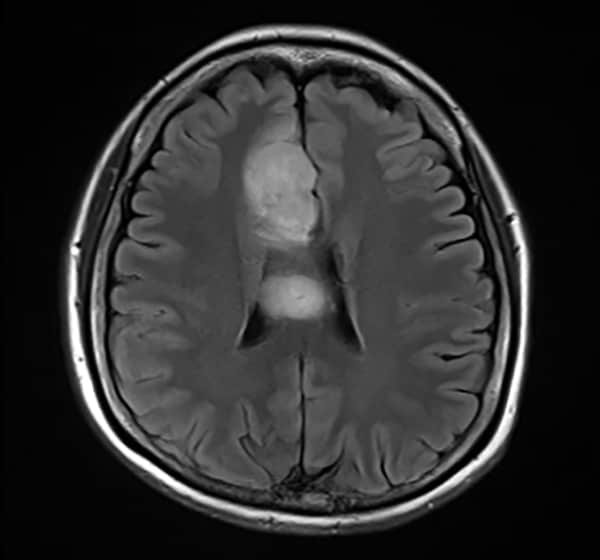

Low grade glioma(oligodendroglioma)

回転性めまいで救急搬送された患者。左上脱力あり。脳卒中を疑いCT/MRI検査したところ、右前頭葉に石灰化を伴う腫瘤を認めた。後日術前精査目的で造影MRI施行となった。

40歳代、女性、50kg、乏突起神経膠腫

脳腫瘍術前精査目的

T1WI低信号、T2WI高信号、FLAIR高信号、DWIでやや高信号の腫瘤。Gdで腫瘤は造影されず、DSC-Perfusionでは辺縁~中心部に一部血流の高い部分あり。MRスペクトロスコピーではCho上昇とNAA低下がみられる。Low grade gliomaを疑う。後日、摘出手術が施行され、病理診断はoligodendroglioma NOS(Grade 2)であった。

当該疾患の診断における造影MRIの役割